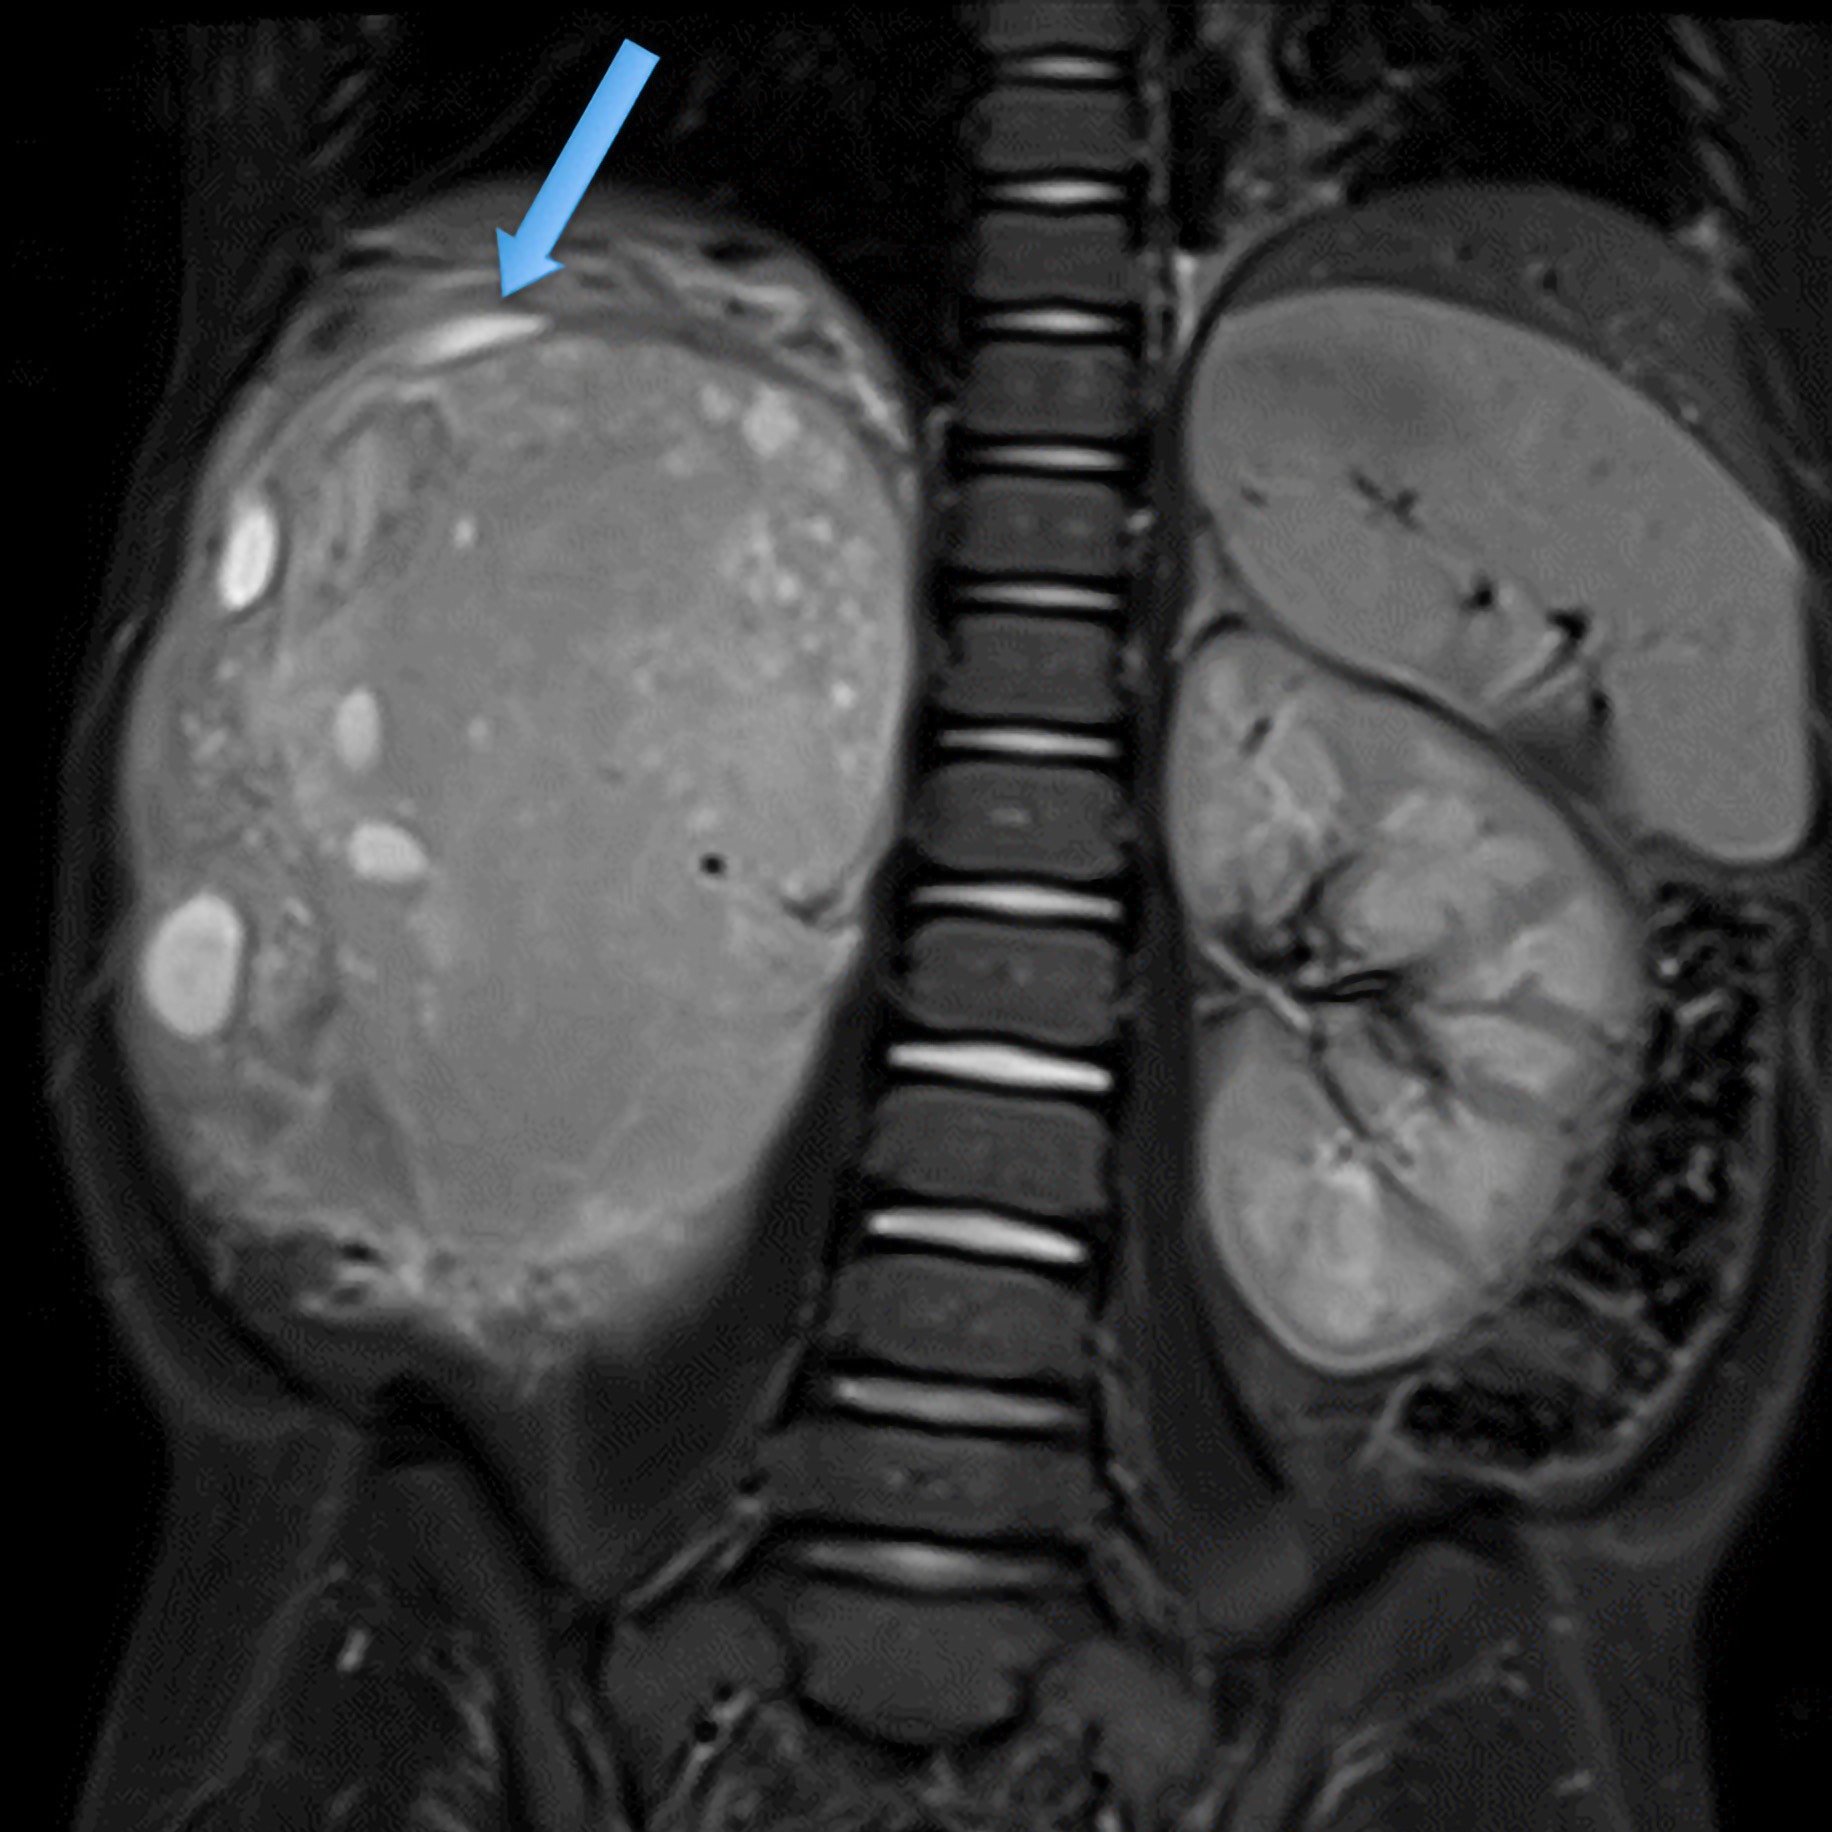

1. Diagnostics: Beyond Morphology

The authors advocate for integrating imaging, molecular, and epigenetic data to enable early detection and treatment personalization:

• Ultrasound, MRI, and CT remain standard imaging tools, but now enhanced with radiomics and 3D segmentation.

1. Radiomics and Advanced Imaging

The review details how radiomic analysis and AI-assisted imaging can predict histological subtypes, therapeutic response, and relapse risk. Coupled with genomic data, they provide the basis for integrative predictive models that will soon guide both surgical planning and post-treatment surveillance.

4. Radiomic features from diffusion-weighted MRI

3.2 Imaging Modalities (5 min)

• Ultrasound: first-line modality

• CT and MRI: for local spread, venous involvement, metastases

• Diffusion-weighted MRI, 3D semi-automated segmentation (e.g., 3D Slicer)

Iconography and Image Processing

BEFORE

AFTER

Faire glisser le slider